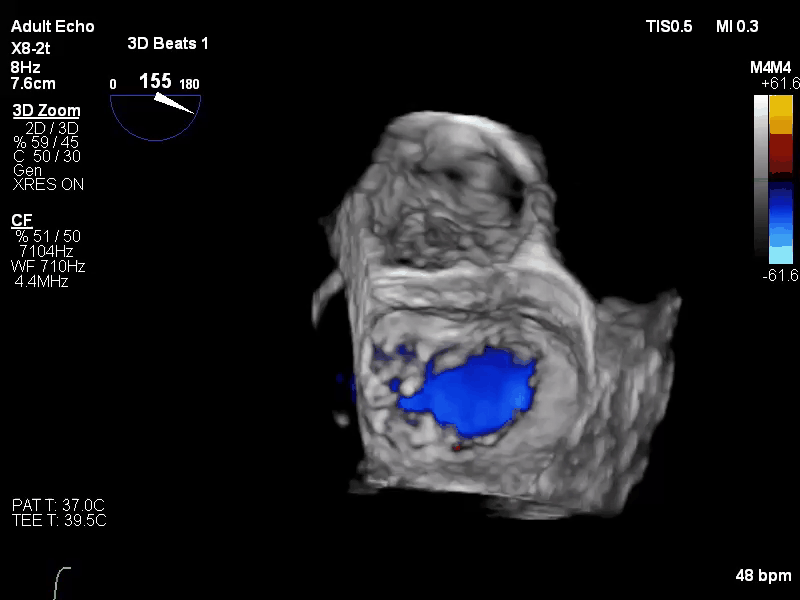

经食道超声心动图(TEE)提示:二尖瓣病变Carpentier II型,DMR,二尖瓣2区反流及P2腱索断裂并瓣叶脱垂,Gap 6 mm,Width 15 mm, 瓣口面积6.7 cm²,2区前叶长20 mm,后叶长19 mm。MR4+,反流束来自于2区,偏心性反流束,指向前叶;VC 11 mm。房间隔穿刺空间约4.5 cm。

术前TEE 3D COLOR

经术前积极抗心衰等治疗,心功能较前改善。术前准备妥后手术于全麻下进行,经右侧股静脉--房间隔途径,4Ch切面确认穿刺高度满意,穿刺房间隔后交换置入Superstiff至左上肺静脉,之后置入导引鞘及夹合器输送系统,在TEE引导下,将2枚G12P型号的夹合器顺利植入到二尖瓣A2/P2区,确定夹合器位置稳定。彩色多普勒超声提示:二尖瓣微量反流,MG 2 mmHg,肺静脉多普勒波形由反向恢复正常,左房压显著下降。多切面证实夹合组织充分后释放,撤除器械输送系统后右侧腹股沟皮肤穿刺口加压包扎,术毕。手术室内超快通道拔除气管插管后送ICU监护。